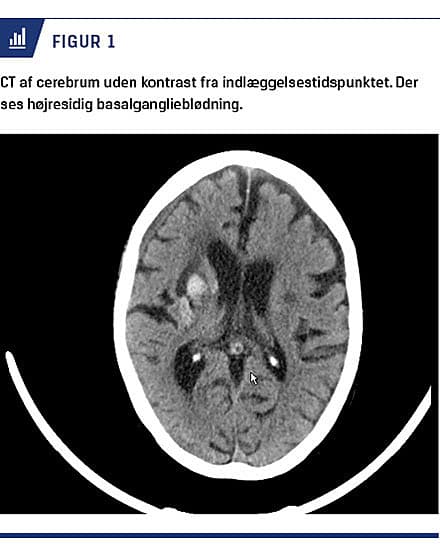

Ved indlæggelse viste en CT af cerebrum en sandsynligvis hypertensionsbetinget hæmoragi i mesencefalon med involvering af højre basalganglieområde og thalamus (Figur 1).